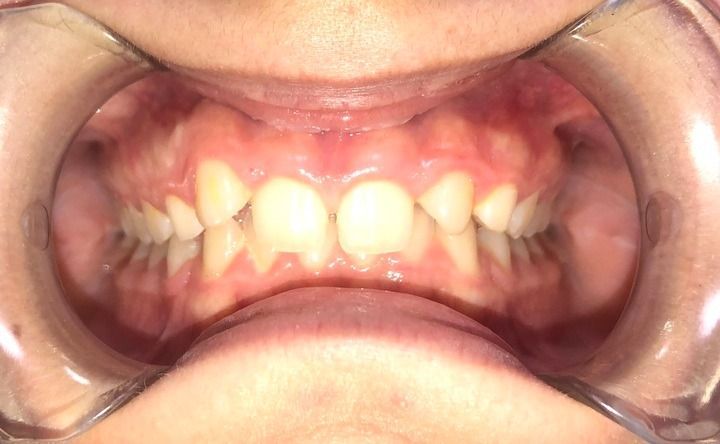

Ortodoncia

Para aquellos que buscan corregir problemas de alineación dental, ofrecemos una variedad de opciones de ortodoncia. Nuestros tratamientos incluyen brackets tradicionales y ortodoncia invisible, que son excelentes soluciones para abordar apiñamientos, espacios entre dientes, problemas de mordida y otros problemas ortodóncicos.

Además, nuestro equipo está capacitado para realizar ortodoncia quirúrgica en colaboración con cirujanos maxilofaciales para casos más complejos que requieren intervenciones adicionales para lograr resultados óptimos.

La agenesia dental es la ausencia de un diente que nunca ha llegado a formarse o desarrollarse. Es un fenómeno común en muelas del juicio e incisivos laterales. Cuando hay agenesia de estos últimos, con ayuda de ortodoncia se conforma el espacio para poder colocar implantes o, si la situación es favorable, se cierran los espacios sin que se note que falta un diente.